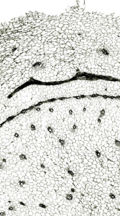

乾姜(カンキョウ)

- 生薬の性状

本品は偏圧した不規則な塊状でしばしば分枝する。分枝した各部はやや湾曲した卵形又は長卵形を呈し、長さ2~4cm、径1~2cmである。外面は灰黄色~灰黄褐色で、しわ及び輪節がある。折面は褐色~暗褐色で透明感があり角質である。横切面をルーペ視するとき皮層と中心柱は区分され、全面に維管束が散在する。 本品は特異なにおいがあり、味は極めて辛い。 本品の横切片を鏡検するとき、外側よりコルク層、皮層、内皮、中心柱が認められる。皮層と中心柱は一層の内皮によって区分される。皮層及び中心柱は柔組織からなり、繊維束で囲まれた維管束が散在する。柔組織中には黄色の油よう物質を含む油細胞が散在し、柔細胞中にはシュウ酸カルシウムの単晶が含まれ、でんぷんはのり化している。

| 乾姜(赤肉干姜) <中国広東省> |

| 維管束 |